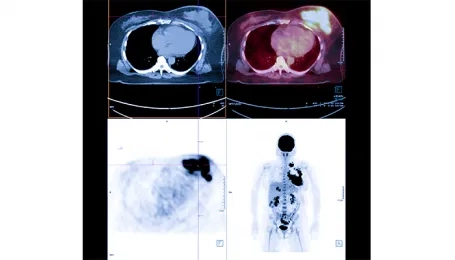

Many different imaging methods can be used in the diagnosis of neuroendocrine tumors, including CT, MR, PET/CT, and ultrasound. PET/CT imaging performed with FDG, a kind of sugar used in the diagnosis of many cancers and in the detection of disease spread, falls short in detecting neuroendocrine cancers. For this reason, special PET/CT scans using smart molecules are used for neuroendocrine cancers. Gallium-68 DOTATATE PET/CT imaging is used to find and image tumor cells in the body at the molecular level. Gallium-68 DOTATATE is accepted as an up-to-date imaging method used for neuroendocrine tumors.